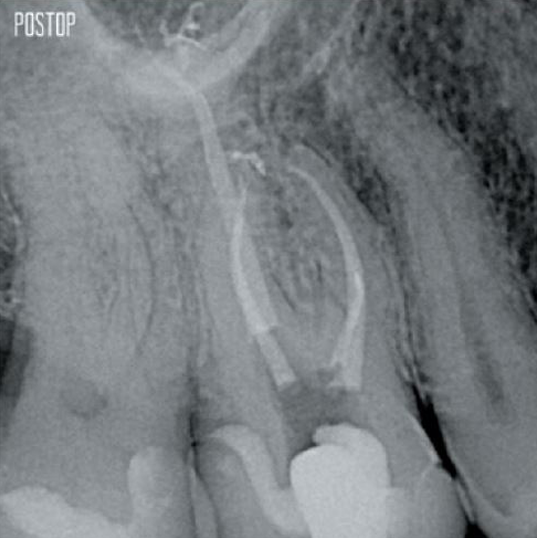

Photos gracieusement offertes par le Dr Ahmed Salman

La dentine de rétention constitue la base essentielle d’une restauration de qualité après un traitement de canal radiculaire. Plus la dentine est préservée au cours d’un traitement endodontique, plus il y a d’options pour réaliser une restauration réussie et durable1.

TruNatomy® est conçue pour préserver autant de dentine que possible1 et offre une solution complète, avec des options d’irrigation et d’obturation adaptées.

Une cavité endodontique conservatrice (CEC) est recommandée avec le système TruNatomy®.

L’accès est désormais possible sous différents angles alors que jusqu’à présent, il fallait sacrifier une structure (carie endodontique traditionnelle)1.

Pas besoin d’un accès en ligne droite1.

L’union de la géométrie de la lime, des cônes régressifs et du fil mince et très flexible permet un traitement efficace du traitement de canal tout en n’enlevant que la dentine là où c’est cliniquement nécessaire1.

Plus de dentine préservée Forme, irrigation et obturation appropriées assurées.